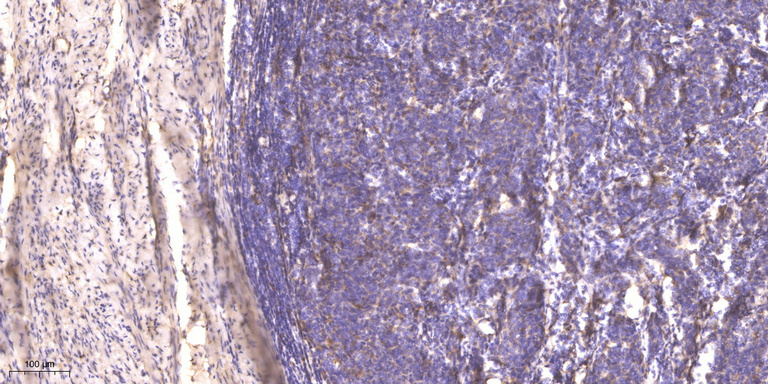

IHC (Immunohistochemistry)

(Immunohistochemical analysis of paraffin-embedded human cervical carcinoma. 1, Antibody was diluted at 1:200(4 degree overnight). 2, Tris-EDTA,pH9.0 was used for antigen retrieval. 3,Secondary antibody was diluted at 1:200(room temperature, 45min).)